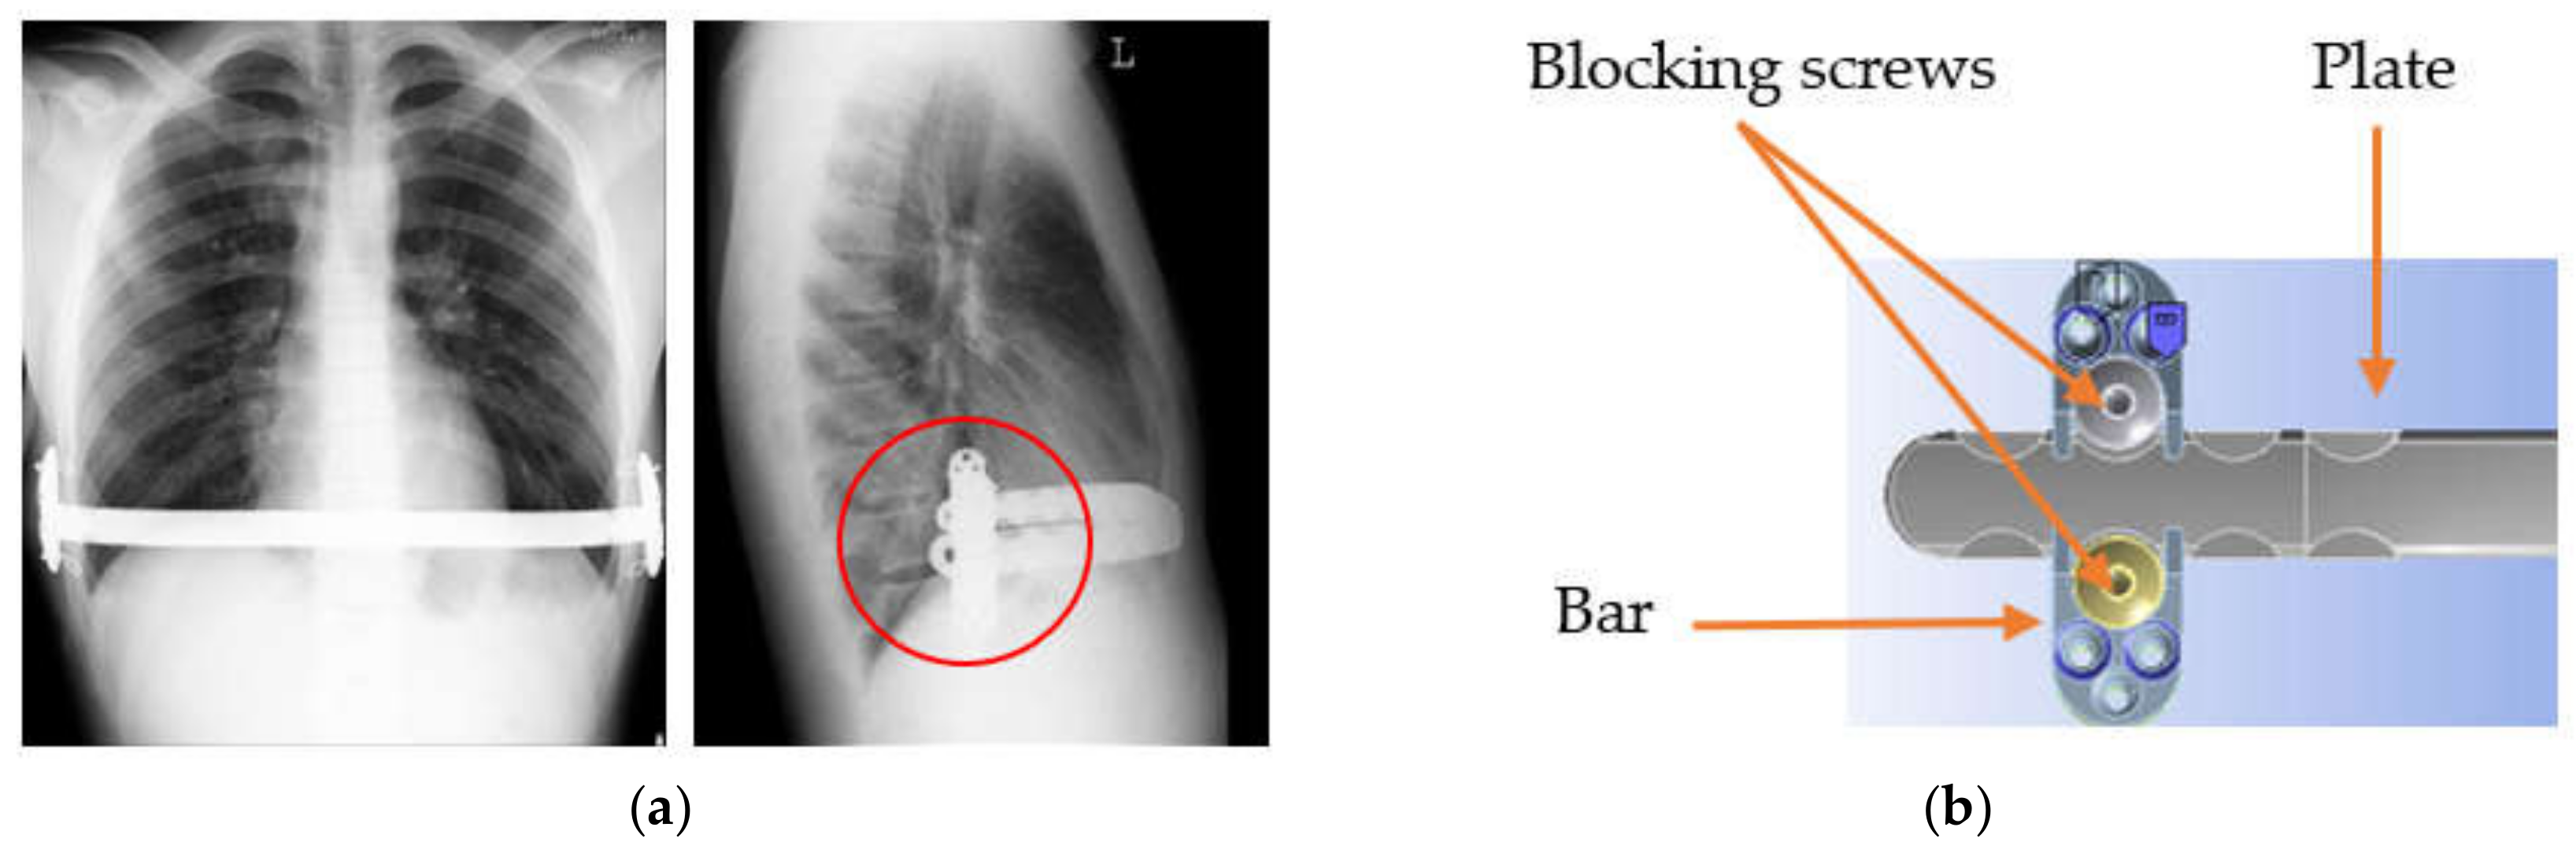

- Kajzer, A.; Głąb, E.; Kajzer, W.; Wróbel, T.; Antonowicz, M. Corrosion Resistance of Stabilizers for Funnel Chest Treatment. Innov. Biomed. Eng. 2017, 526, 25–32. [Google Scholar]